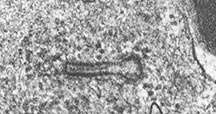

- Birbeck Granules: Electron Microscopy demonstrates granules that often take the form of a tennis raquet and form from complex invaginations of the cell membrane